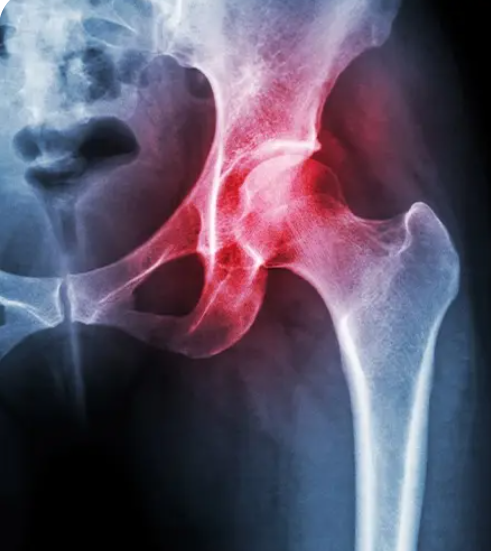

Total Hip Replacement

Hip Fracture

Trochanteric Bursitis

Hip Labral Tear

Hip Impingement

Hip Osteoarthritis